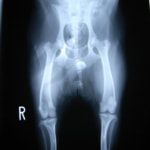

■ 症例24 キャバリア 7か月

左右膝蓋骨内方脱臼(左:グレードⅣ 右:グレードⅢ)

以前から左右後肢の跛行が認められ、整形外科学的検査・レントゲン検査により左右の膝蓋骨脱臼が認められた。症状が重度である左膝の膝蓋骨脱臼整復術を行った。外科手技は縫工筋及び内側広筋の解放、脛骨粗面の外側転位、滑車ブロック形造溝術、内外側関節方の縫縮を実施した。術後一か月時点で、左の膝蓋骨は安定しており経過は良好である。

本症例は成長期における重度の膝蓋骨脱臼であり、術後の再発の可能性もあるため、経過をしっかりと観察していく必要がある。また、今回手術を実施していない右膝に関しても経過を観察し、手術を検討していくこととする。